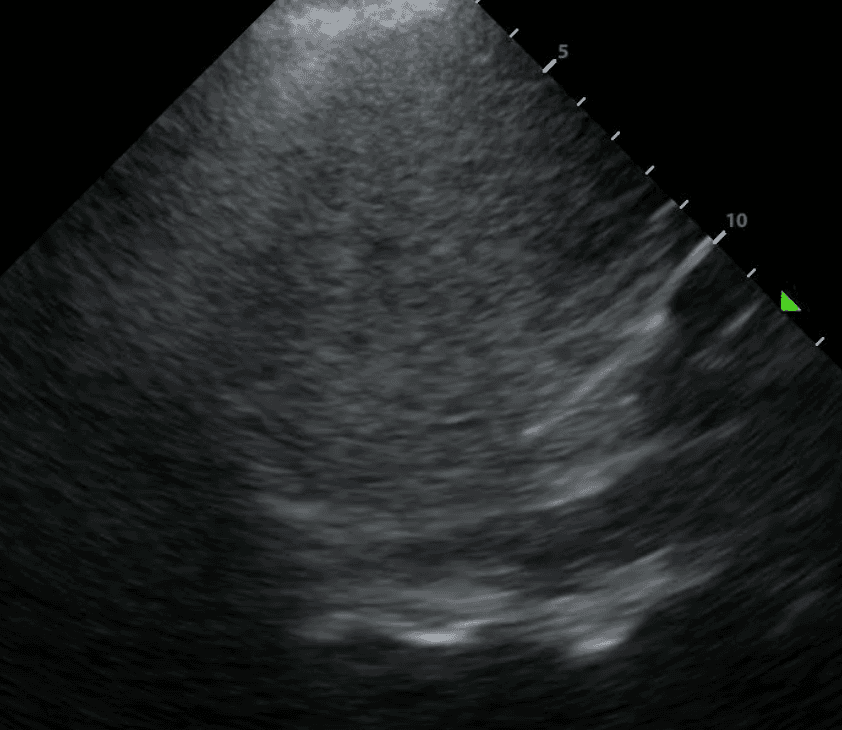

Some features of a simple effusion include:

In contrast to exudative effusions, a thoracentesis may not be necessary for a transudative effusion unless there is compressive atelectasis or the effusion has not resolved by treating the suspected cause.